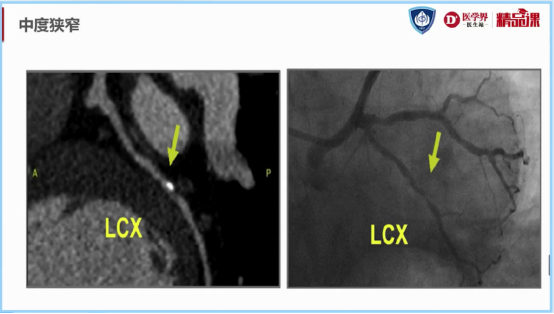

图8:中度狭窄(50-69%)示意图